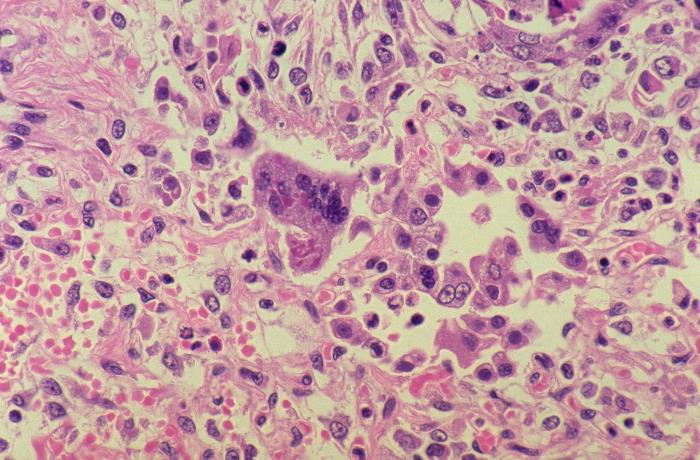

Ryc. A – badanie histopatologiczne tkanki płuca, na którym w części centralnej zostały uwidocznione komórki olbrzymie. Tkanka płuc dodatkowo infiltrowana jest przez liczne komórki układu immunologicznego (małe fioletowe komórki). Dodatkowo widać w polu widzenia sporą ilość erytrocytów, co sugeruje przekrwienie tkanki płuc. Całość obrazu odpowiada niebakteryjnemu zapaleniu płuc, a komórki olbrzymie sugerują, że winowajcą jest Morbillivirus.